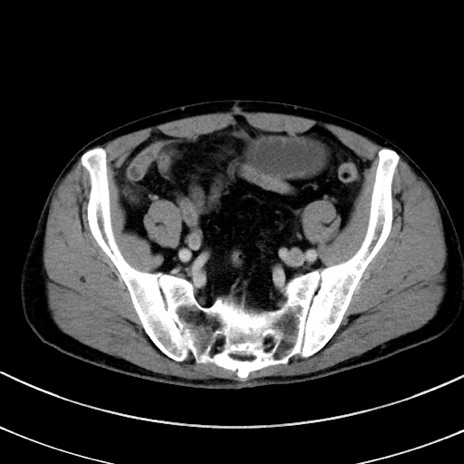

症例8(横断像)

【症例】 60歳代男性

【主訴】 黒色吐物

【現病歴】 4日前から嘔気自覚、2日前の朝食後にも嘔気あり、自分で手で嘔吐反射起こし嘔吐したところ血が混ざっていたため受診。

【既往歴】 5年前汎発性腹膜炎を伴う急性虫垂炎で手術、高血圧、前立腺肥大症、高脂血症

【身体所見】 腹部正中に手術癩痕あり 腹部平坦・軟圧痛なし膨満感あり

【データ】WBC 8400、CRP 4.54